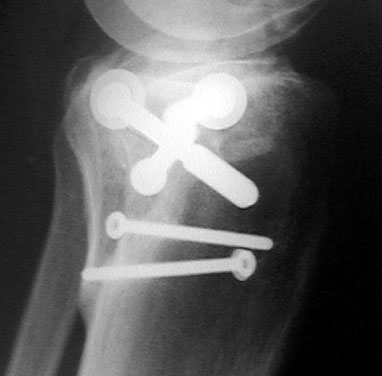

Dazu als Vergleich das Röntgenbild vom 23. Mai 2001; Beginnende Einheilung der Emimnenz (1) sowie deutliche Frakturstelle in der Gelenkfläche (2).

Röntgenbild (Seitenansicht) vom 7. Juli 2001. Das am linken Rand des Schienbeinkopfs sichtbare, vorstehende Teil sollte im Lauf der Zeit wieder besser einwachsen.